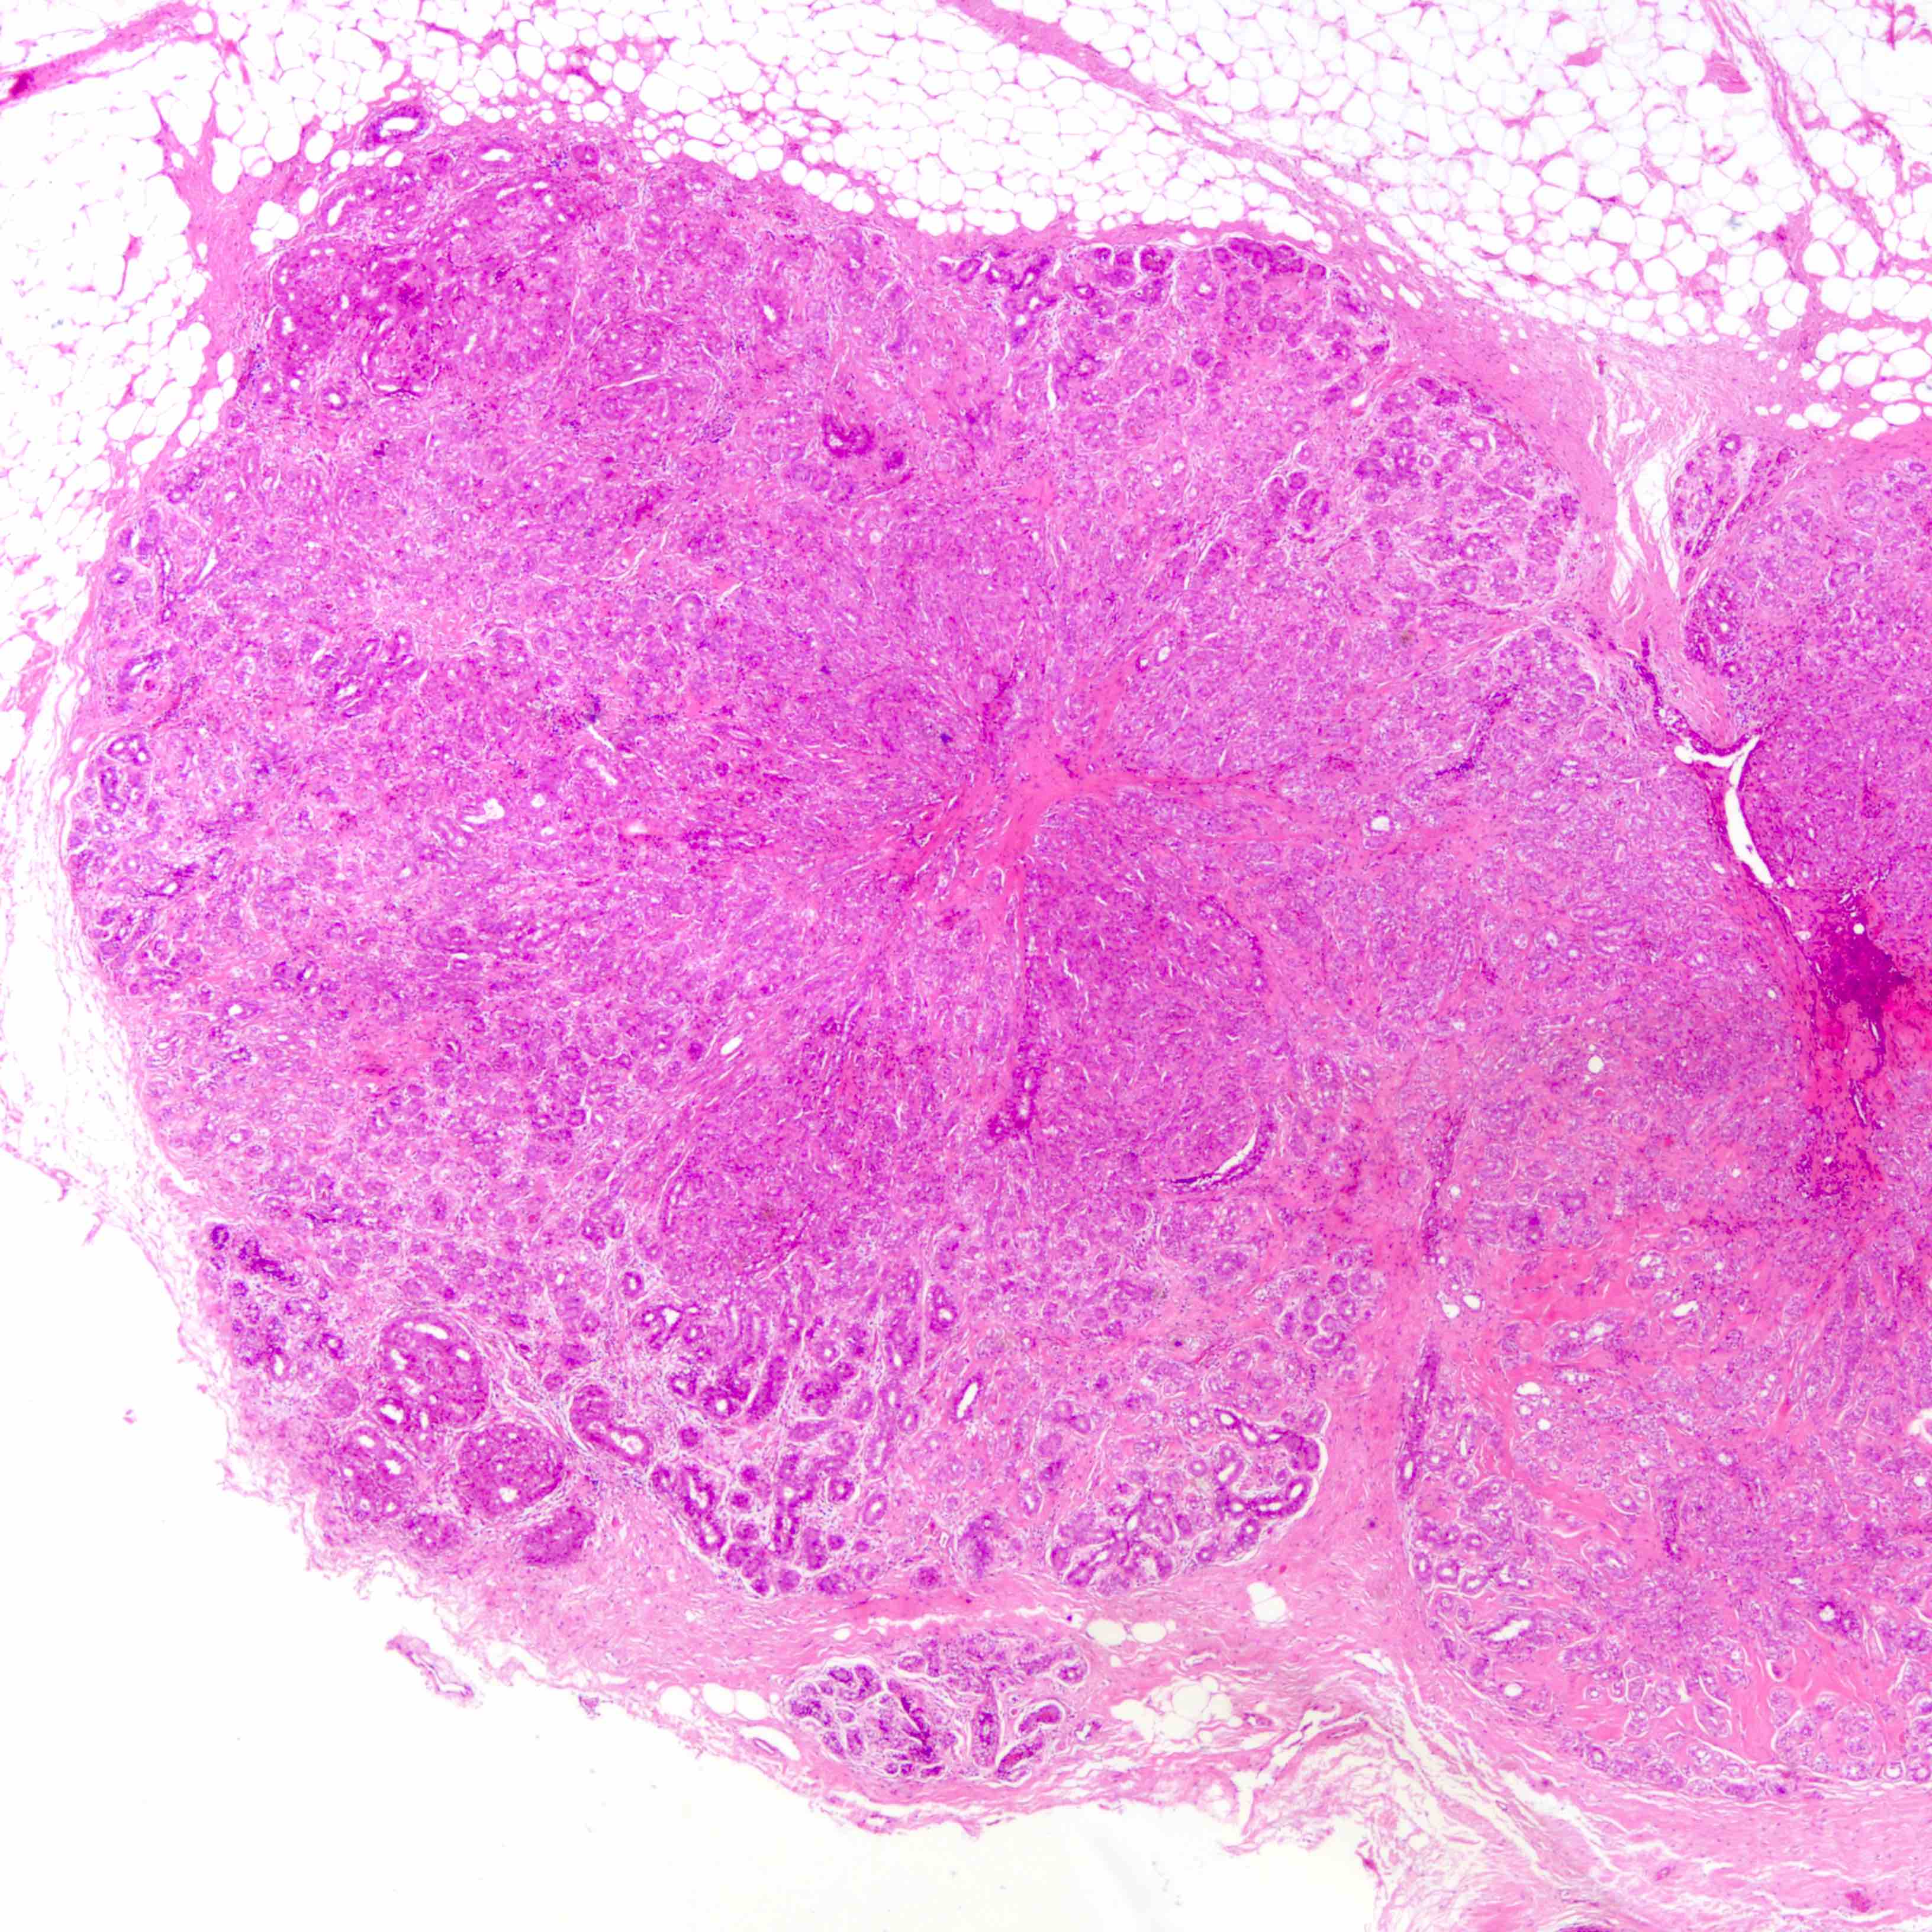

- Well defined borders

- Sparse fibrovascular stroma intervening tubules

- Small, uniform, closely packed round tubules (Clin Med Insights Pathol 2018;11:1179555718757499)

- Lined by an inner layer of luminal epithelial cells and an outer layer of myoepithelial cells

- Rare mild atypia and mitotic figures does not exclude diagnosis

- Occasional luminal eosinophilic secretion

Microscopic (histologic) images

Contributed by Joshua J.X. Li, M.B.Ch.B. and Gary M. Tse, M.B.B.S.

Contributed by Jijgee Munkhdelger, M.D., Ph.D. and Andrey Bychkov, M.D., Ph.D.